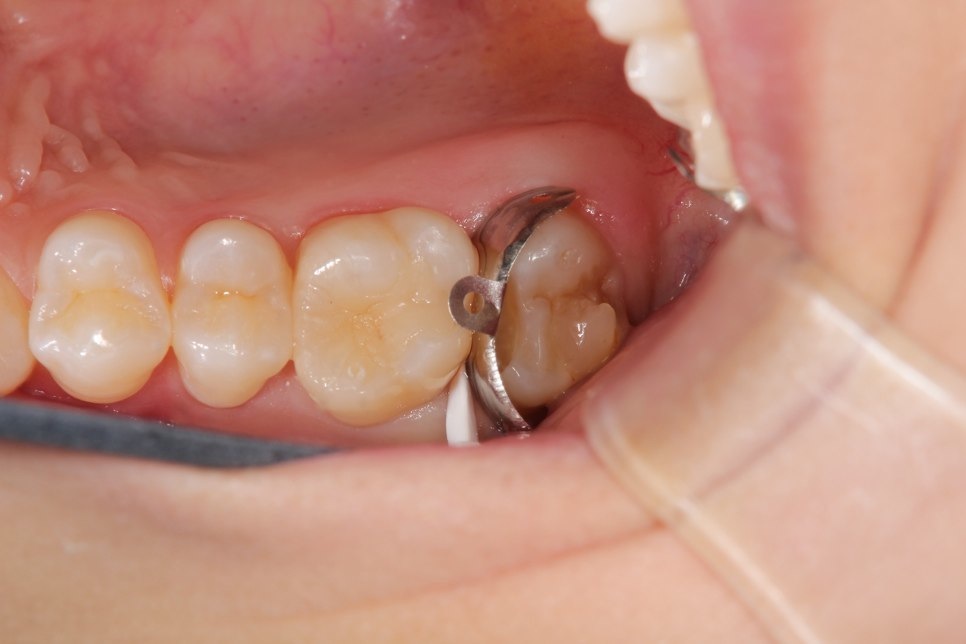

前歯の虫歯です。唾液の量が多い方や歯ぐきから出血がある方にはラバーダム防湿法を使います。このように緑色のゴムのシートを使用して、歯に唾液や血液が付かない様にします。

虫歯をとったところです。

無事治療が終わりました。削った穴に唾液や血液が入り込むと接着力が低下してしまいます。今回、削った穴に汚れが付く事無く、審美的な治療が出来ました。

ダイレクトボンディング

費用2万円×2本

リスクとして変色や欠ける可能性がある(修復可能)。